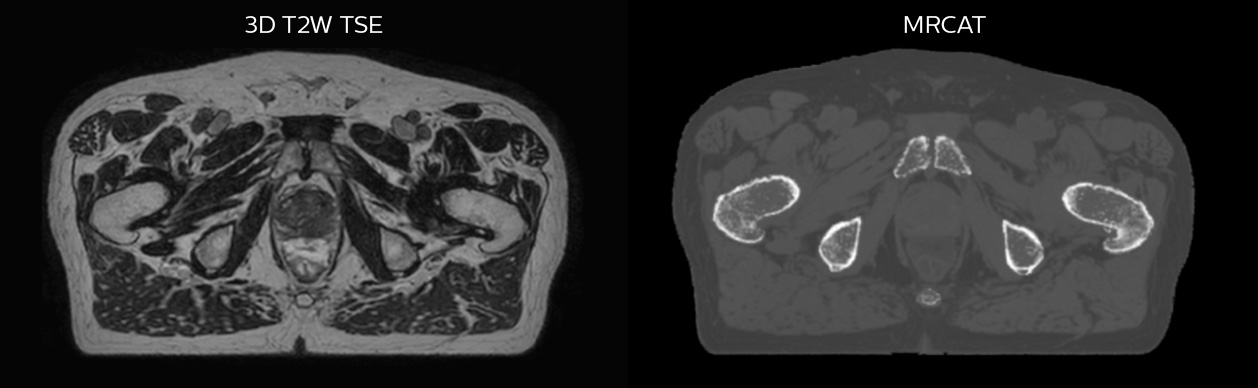

Hôpital de La Tour uses an implanted rectal spacer (SpaceOAR®, Boston Scientific) for patients receiving prostate radiotherapy to provide space between the rectum and prostate. 3D T2W TSE MRI provides excellent rectal spacer visualization and is used for OAR and target contouring. The dose plan is calculated on the MRCAT dataset.

Simulation imaging

Tranversal 3D T2W TSE with Compressed SENSE, acquired on Ingenia MR-RT 1.5T (left).

On-console generated MRCAT (right).

MR-based contouring and planning

MRCAT is primary image dataset for dose calculation (left).

3D T2W TSE MRI with 36 cm Field-of-View is used for delineation of prostate and organs at risk (right).